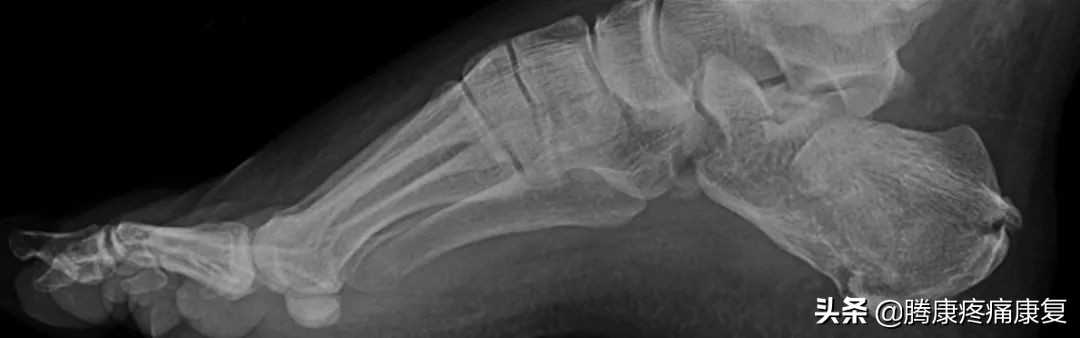

高足弓是什么

高足弓又称为弓形足,这是一种足弓异常升高的形态,当双脚均匀地站立时,由于足弓中部向上抬起,重力全部都集中在脚跟和脚掌上,最终会导致足部疼痛、鸡眼和老茧、足弓僵硬和小腿肌肉紧张。

高足弓大多数都是由先天家族遗传引起的,但是也有一部分人会因为后天生活中的各种问题导致高足弓,如果是后天产生的高足弓,这有可能是一些神经系统疾病所引起的,例如腓骨肌萎缩症。